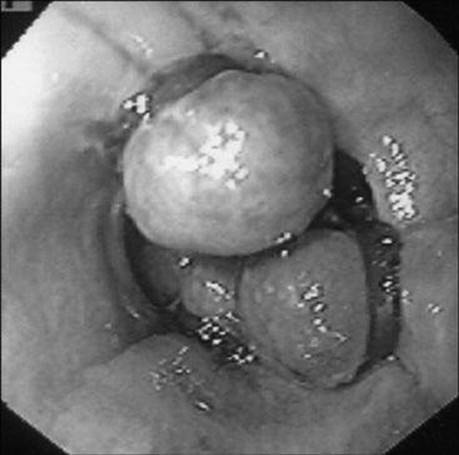

A 37-year-old man with a history of alcohol abuse is transferred to your hospital with a history of hematemesis and melena the day before. He has numerous spider telangiectasias on his upper body and mild asterixis. What lesion is being demonstrated on upper endoscopy?

Figure 1-1

Esophageal varices in the distal esophagus that have undergone band ligation.